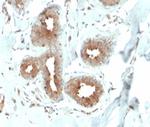

Antibodies that detect Mammaglobin can be used in several scientific applications, including Immunohistochemistry, Peptide array, Western Blot, Immunocytochemistry and ELISA. These antibodies target Mammaglobin in Human samples. Our Mammaglobin recombinant monoclonal,... Antibodies that detect Mammaglobin can be used in several scientific applications, including Immunohistochemistry, Peptide array, Western Blot, Immunocytochemistry and ELISA. These antibodies target Mammaglobin in Human samples. Our Mammaglobin recombinant monoclonal, monoclonal and polyclonal antibodies are developed in... Antibodies that detect Mammaglobin can be used in several scientific applications, including Immunohistochemistry, Peptide array, Western Blot, Immunocytochemistry and ELISA. These antibodies target Mammaglobin in Human samples. Our Mammaglobin recombinant monoclonal, monoclonal and polyclonal antibodies are developed in Rabbit and Mouse. Find the Mammaglobin antibody that fits your needs. Choose from 1 of 27 Mammaglobin antibodies, which have been validated in experiments with 79 images featured in our data gallery.

Antibodies that detect Mammaglobin can be used in several scientific applications, including Immunohistochemistry, Peptide array, Western Blot, Immunocytochemistry and ELISA. These antibodies target Mammaglobin in Human samples. Our Mammaglobin recombinant monoclonal, monoclonal and polyclonal antibodies are developed in Rabbit and Mouse. Find the Mammaglobin antibody that fits your needs. Choose from 1 of 27 Mammaglobin antibodies, which have been validated in experiments with 79 images featured in our data gallery.

Current literature indicates that mammaglobin, as measured by the ELISA, holds significant promise for breast cancer screening with the realistic potential to impact management of this disease.